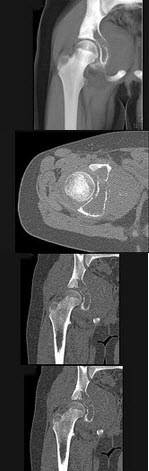

19、单项选择题

男,5岁,髋部疼痛乏力伴跛行5个月,结合图像,最可能的诊断是()

A.髋关节结核

B.骨肉瘤

C.股骨头骨骺缺血坏死

D.骨囊肿

E.软骨肉瘤